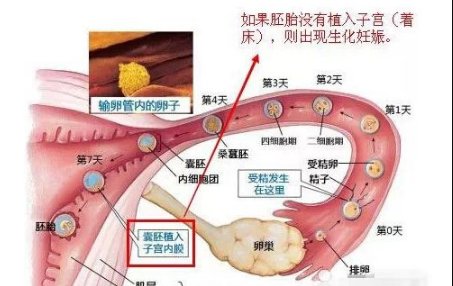

这种情况最常见,怀孕早期,胚胎本来就不稳定,受精卵着床、胚胎发育不良等就容易出血,若再加上过度劳累、提重物、走路多、同房、剧烈运动等外因的刺激,就更容易出现见红。

1、受精卵着床

受精卵着床时,会刺激子宫内膜引起少量出血,当然是不是这种情况需要去医院做检查排查。

2、生化妊娠、流产、胎停

怀孕早期会有“优胜劣汰”的选择,因而如果胚胎本身质量不好,会在孕早期被“淘汰”掉,就会发生生化妊娠、流产、胎停等。

② 刚查出怀孕时间不长就出血,像来月经一样的出血,去做B超,若检查发现子宫内没有孕囊,这就是生化了,胎儿也就保不住了;